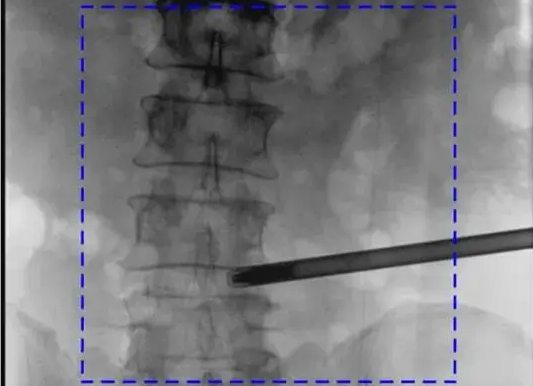

【CAOS2025骨科医师年会】普爱医疗举办骨科手术机器人实操体验活动

第十六届中国医师协会骨科医师年会(CAOS 2025)于2025年6月19日-22日在湖南长沙举行。普爱医疗携骨科手术机器人与骨科影像解决方案亮相,同步开展设备实操体验,邀请骨科手术机器人临床应用专家演示指导,为参会者提...